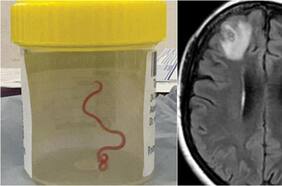

El parásito, que infecta principalmente a las ratas, puede invadir el cerebro humano a través de la ingesta de alimentos. Es originario de China, pero ya se encuentra en gran parte del sudeste de Estados Unidos y los científicos están preocupados por su propagación.

Inquietud por detección de peligroso gusano que portan ratones y que puede infectar tu cerebro